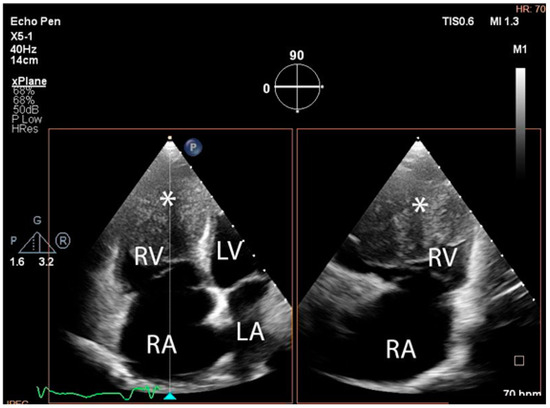

The troponin I level was found to be slightly elevated (90 ng/mL). Coronarography was used to rule out any luminal or anatomical abnormalities. A tumour filling the right ventricle and involving the apex of the left ventricle was identified at transthoracic echocardiography (Figure 3 and Figure 4).

Figure 3. Transthoracic echocardiographic apical four-chamber view: a larger mass (∗) in the right ventricle which also involves the apex of the left ventricle. (Abbreviations: RA = right atrium, LA = left atrium, RV = right ventricle, LV = left ventricle, (∗) cardiac mass.)

Diagnostics 14 00919 g003

Figure 4. Transthoracic echocardiographic, biplane view of the right ventricle; note the mass (∗) that displaces a significant part of the cavity. (Abbreviations: RA = right atrium, LA = left atrium, RV = right ventricle, LV = left ventricle, (∗) cardiac mass.)

Diagnostics 14 00919 g004